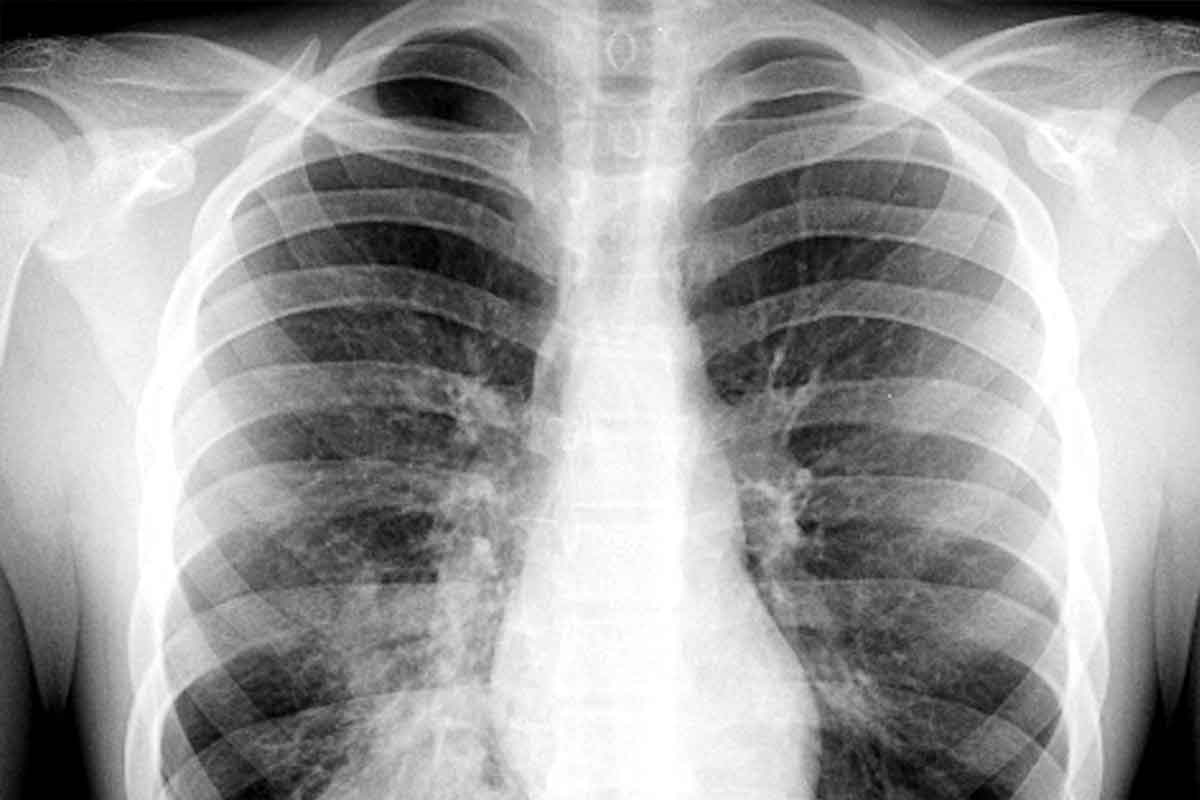

Imaging Techniques

Imaging, like chest X-rays, is key for diagnosing PNA. It helps us see lung problems and how widespread they are.